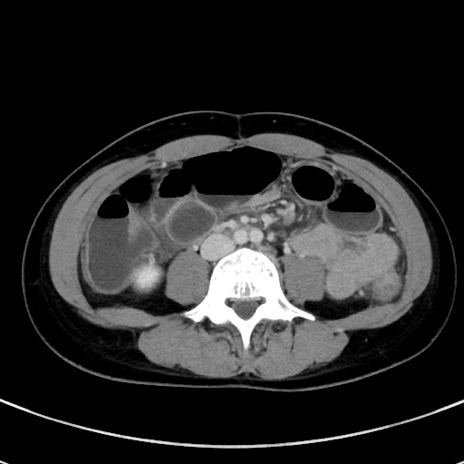

症例17(横断像)

【症例】20歳代女性

【主訴】嘔吐、下腹部痛

【現病歴】昨日夕食後に嘔吐し下腹部痛が出現。本日になっても嘔吐持続し改善しないため来院。

【身体所見】意識清明、BT 37.2℃、BP 108/67mmHg、腹部:平坦、やや硬、下腹部正中から右にかけて圧痛あり、反跳痛軽度あり、tapping pain(+)。

【データ】WBC 13600、CRP 14.94